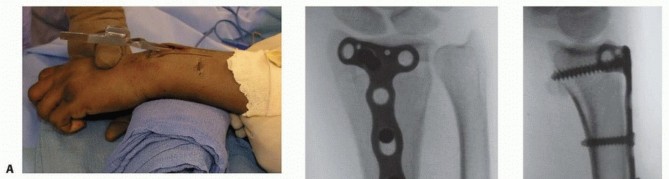

TECH FIG 2 • A. Reduction maneuver. The distal radius is reduced over a bump of towels using traction and palmar displacement of the carpus. B. Plate placement. The plate is placed deep to the EPL and aligned distally over the distal radius. C,D. Reduction imaging. C. PA fluoroscopic view demonstrating final reduction with well-aligned plate. D. Lateral fluoroscopic view demonstrating final reduction with appropriate-length screws and good distal buttressing of the fracture. Volar tilt has been restored. Bone graft is inserted to support reduced articular fragments and then the dorsal plate is applied directly on the radius ( TECH FIG 2B). The plate is first secured with a bicortical screw inserted through the oval sliding hole. Fracture reduction and placement of the plate are confirmed using fluoroscopy. The plate is secured to the distal fragment with one or two cancellous screws. Depending on the implant used, the surgeon should avoid placing the distal ulnar screw through the plate as the prominence of the screw head may irritate the overlying digital extensor tendons in the fourth dorsal compartment.

Additional cortical screws are added in the radius shaft. Reduction and stability are confirmed ( TECH FIG 2C,D). Wound Closure The wound must always be copiously irrigated. The retinaculum is closed deep to the transposed EPL tendon, incorporating the periosteal layer that forms the floor of the extensor compartments ( TECH FIG 3A). The skin is closed with nylon suture ( TECH FIG 3B). Finally, a short-arm volar splint is applied over a sterile dressing. Care should be taken to extend the splint to, but not across the distal transverse palmar flexion crease, in order to reduce the risk of postoperative intrinsic muscle and finger joint contractures.